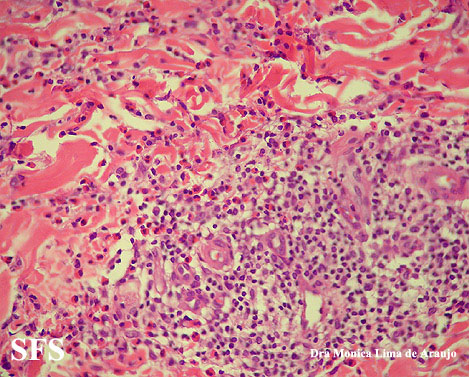

eosinophilic annular erythema